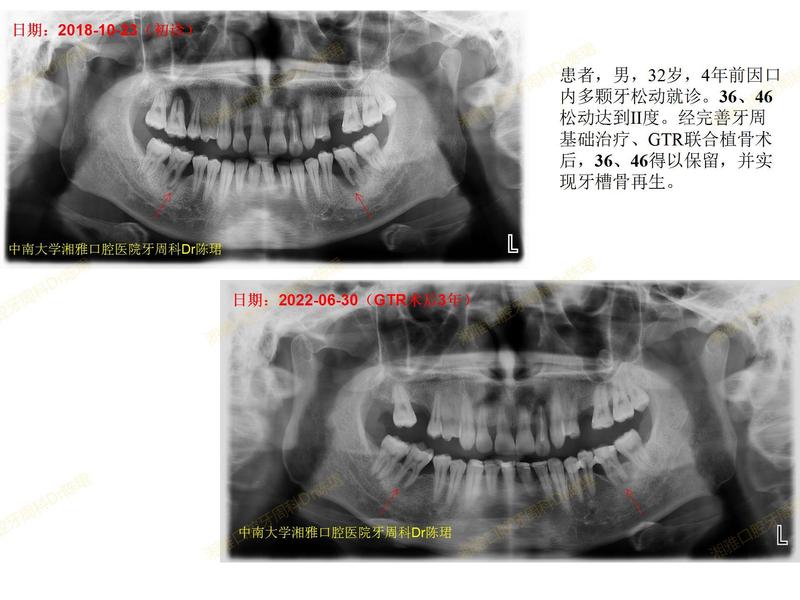

患者,男,32歲,4年前因口內(nèi)多顆牙松動就診。36、46松動達到II度。經(jīng)完善牙周基礎治療、GTR聯(lián)合植骨術后,36、46實現(xiàn)牙槽骨再生,得以保留。好的療效也離不開患者幾年來一直堅持定期牙周維護??。PS:22牙4年前就松動III度,患者說要堅持到種植牙集采再拔再種??